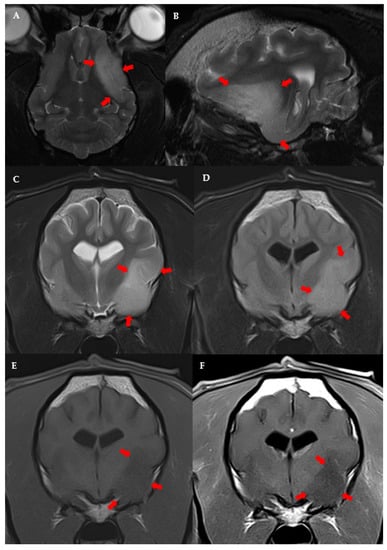

3.3. MRI Features and Localisation of Suspected Glioma